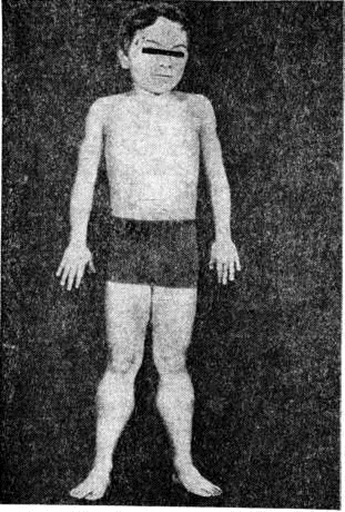

Ведущими симптомами заболеваний этой группы являются повышенная утомляемость и слабость мышц, симметричные мышечные атрофии, снижение или отсутствие сухожильных рефлексов. При отдельных формах заболевания отмечается псевдогипертрофия (рисунок 3), когда объем поражённых мышц увеличен, хотя сила их снижена так же, как при атрофии. При локализации миодистрофического процесса в области лица мимика больных становится бедной. Гипомимия приводит к характерному выражению лица — «миопатическое лицо». Следствием атрофии круговой мышцы рта является «поперечная улыбка». Губы утолщены и несколько вывернуты кнаружи — «губы тапира». На лбу отсутствуют морщины — симптом «полированного лба».

Миопатия Дюшенна — прогрессирующая мышечная дистрофия, ранняя детская, проксимальная, псевдогипертрофическая, рецессивная, сцепленная с Х-хромосомой. Болеют мальчики. Аналогичное заболевание, встречающееся у девочек, считают псевдогипертрофической аутосомно-рецессивной формой. Характерной особенностью патоморфологические изменений в мышце уже на ранних стадиях процесса является разрастание жировой и соединительной ткани и замещение ими мышечной, чем и объясняется наличие псевдогипертрофии. Заболевание характеризуется появлением слабости и атрофии мышц в возрасте до 3 лет, злокачественным течением и наличием псевдогипертрофий, особенно в икроножных мышцах. У больных могут быть нейроэндокринные нарушения в виде ожирения, гипергидроза и другие